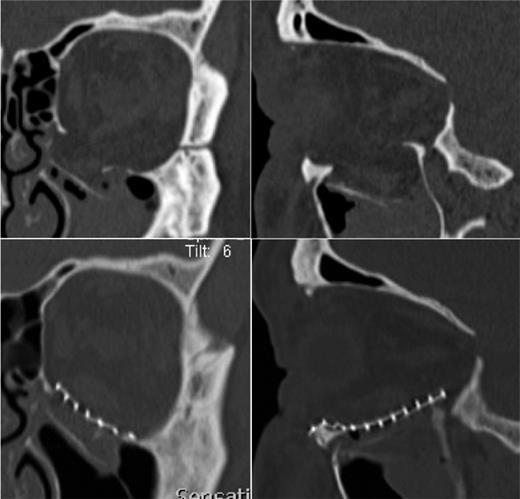

A postoperative CT scan showed a good position of the titanium mesh, as well as repositioning of herniated tissues, but highlighted a tear of the IR muscle in its middle part.

Accordingly, the preoperative CT scan was re-evaluated in 0.5 mm slices and the pre-existence of the ruptured IR was shown (Fig. 3). After ophthalmological consultation and treatment of the patient with a combination of orthoptics and prismatic glasses, satisfactory functional recovery was achieved after 6 months without need of surgical repair of the ruptured muscle.

The preoperative 0.5 mm sliced CT of the orbit presents the tear of the IR muscle in his middle part.